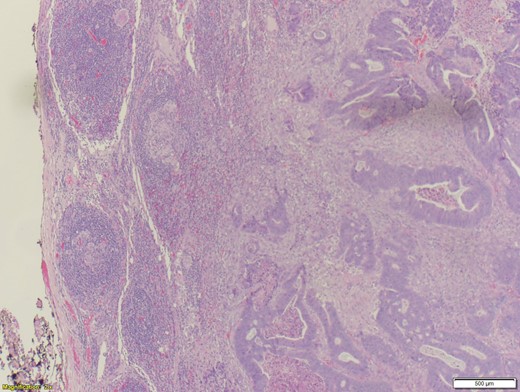

A 70-year-old female presented to the emergency department with complaints of diarrhea, vague, dull abdominal pain, unintentional weight loss and poor appetite. No hematochezia or melaena stated. Fecal occult is strongly positive in the ED. No endoscopies were found in her records. PMHx included COPD, osteoarthritis and DVT. Significant physical exam findings included mild, diffuse abdominal tenderness and RUQ palpable mass, and normal bowel sounds. Labs were significant for a hemoglobin of 5.7, hematocrit of 18.6% and CEA of 29.6. An abdominal/pelvis CT exhibited a 6 cm circumferential mass of the hepatic flexure (Figs 1–3). Two days later, a right hemicolectomy with en bloc pancreaticoduodenectomy was performed. Pathology showed adenocarcinoma stage IIIc (Figs 4–10). Post-operatively, an abdominal/pelvis CT showed bilateral pulmonary emboli and a 14 cm pelvic abscess. Bilateral lower extremity ultrasound showed low probability for DVT. Exploratory laparotomy was performed where the pelvic abscess was seen and extensive lysis of adhesions, resection of ileocolonic anastomosis for contained leak and ileostomy performed. Approximately 4 months after discharge, the patient passed away while in a long-term care facility.